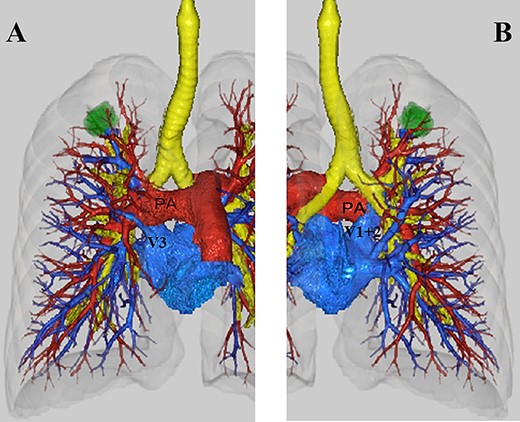

A 62-year-old woman was referred to our hospital due to suspected lung cancer. The chest CT revealed a 32-mm solid pulmonary nodule in the right upper lobe without lymph node enlargement (Fig. 1). The 3D-CT revealed that the right upper pulmonary vein (V1 + 2) ran posterior to the pulmonary artery and anterior to the bronchus intermedius (Fig. 2A and B). On the other hand, anterior segmental vein (V3) had venous return anterior to the top of hilum. Based on this information, we performed right upper lobectomy with systemic lymph node dissection under VATS. Intraoperative findings showed that the V1 + 2 drained to the left atrium between the main pulmonary artery and the bronchus intermedius (Fig. 3), which was clearly detected by the preoperative 3D-CT. We exposed the pulmonary vessels at the hilum and V3 was found superiorly on the most ventral side of the hilum, whereas we could not identify V1 + 2, which is usually located anterior to the hilum. After the V3 and the ascending pulmonary artery were ligated, we recognized the V1 + 2 at the dorsal side of the main pulmonary artery. The anomalous V1 + 2 were isolated and ligated with a vascular stapler. Therefore, it was possible to complete VATS lobectomy without any complications. Pathological examination showed adenocarcinoma with no lymph node metastasis. The postoperative course was uneventful, and the patient was discharged on postoperative day 7.

(A) Anterior view on three-dimensional computed tomography (3D-CT). V1 + 2 ran behind the pulmonary artery. V3 was located superiorly on the most ventral side of the hilum. (B) Posterior view on 3D-CT. V1 + 2 ran in front of the bronchus (PA: main pulmonary artery).